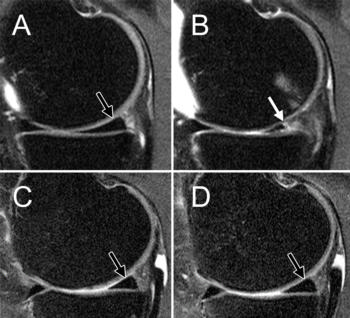

Figure 2. MRIs of the right knee obtained with the coronal proton density–weighted fast spin-echo fat-suppression sequence at, A, C, baseline and, B, D, after 48 months. Patients were an obese 65-year-old woman with stable weight and mild knee pain (Western Ontario and McMaster Universities Arthritis Index (WOMAC) pain subscale score of 3 at baseline; baseline BMI, 33.1 kg/m2) (A and B) and an obese 64-year-old woman with weight loss over 48 months and mild knee pain (approximately 10.9 percent decrease in BMI; WOMAC pain subscale score of 5 at baseline; baseline BMI, 33.7 kg/m2) (C and D). The woman with stable weight developed a full-thickness focal cartilage defect at the medial tibia (arrow) (baseline cartilage Whole-Organ Magnetic Resonance Imaging Score (WORMS) grade 0 in A and 2.5 in B). In contrast, no cartilage defects were detected at baseline or 48-month follow-up in the woman with weight loss (cartilage WORMS grade 0 in C and D).